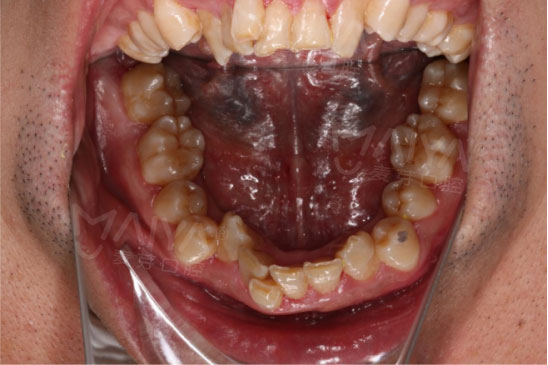

我的牙齿到底可怕到什么程度?前方高能预警———不要被吓到哦

身为公司管理层,平时待人接物不仅仅代表自己,还代表着公司形象,一口鲨鱼牙怎能为麦芽代言?而且注重仪表的我,怎能允许自己在洽谈时露出钢牙套?于是我决定立即在麦芽开始隐形矫牙之旅。